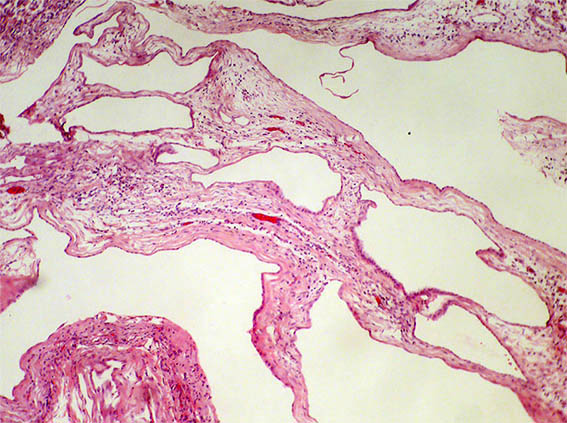

Figura 3.

H&E, X100.